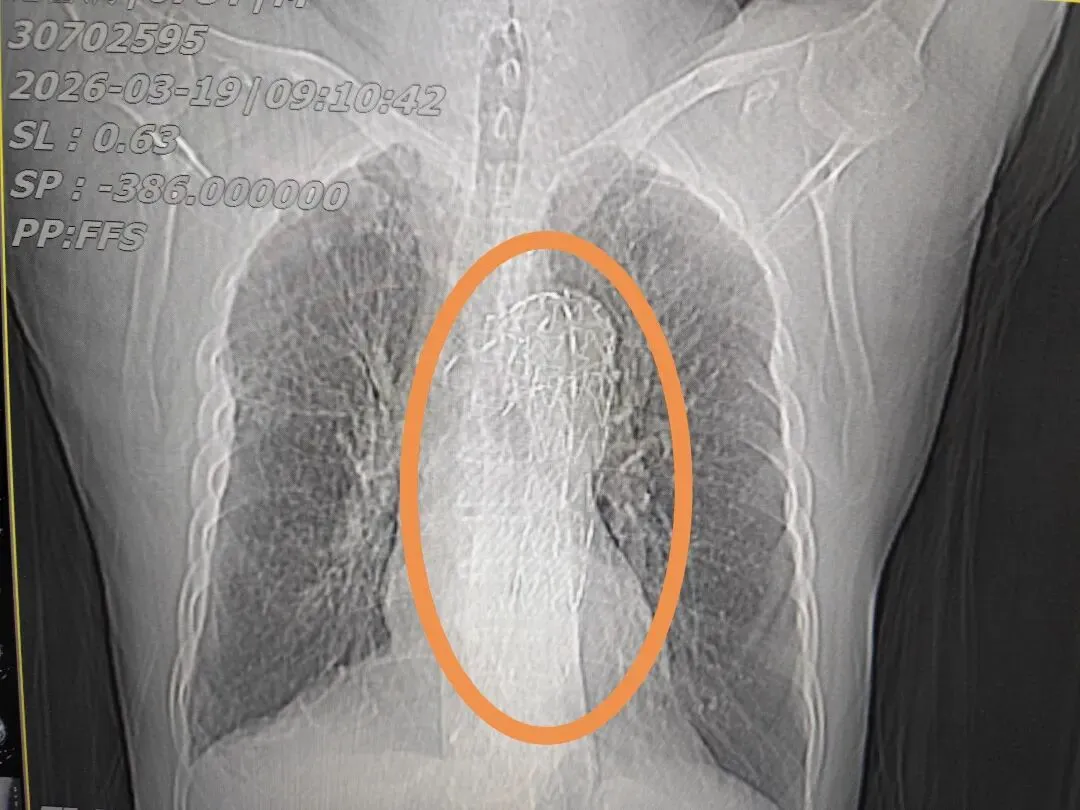

75岁张先生,3年前在当地县医院检查发现右上肺占位性结节,近期复查CT提示结节较前增大,经熟人介绍前来就诊。患者肺部结节直径约1.9cm,体积并不算大,但基础情况十分复杂。

患者7年前曾因车祸接受手术治疗,有多年高血压病史,2年前更因急性主动脉夹层植入主动脉支架。这类手术风险高、创伤大,常被形象地形容为“在胸腔大血管里放一辆‘小车’”,足以说明病情凶险、手术难度与花费均较高。

有个金属网格就是血管支架